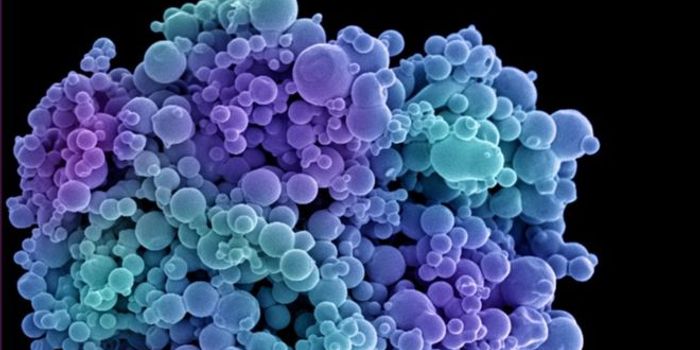

MAY 02, 2024CancerWe interact with small, single-cell organisms on a regular basis. These tiny cells, known as bacteria, represent a ...